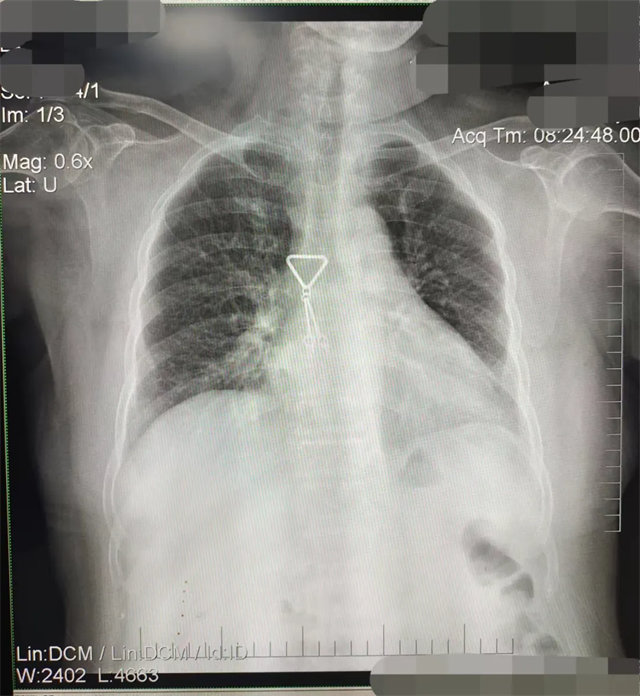

缺陷:雙側(cè)胸鎖關(guān)節(jié)不對稱,且有手機顯影。

解決:去除手機后,使患者左側(cè)緊貼成像件曝光。